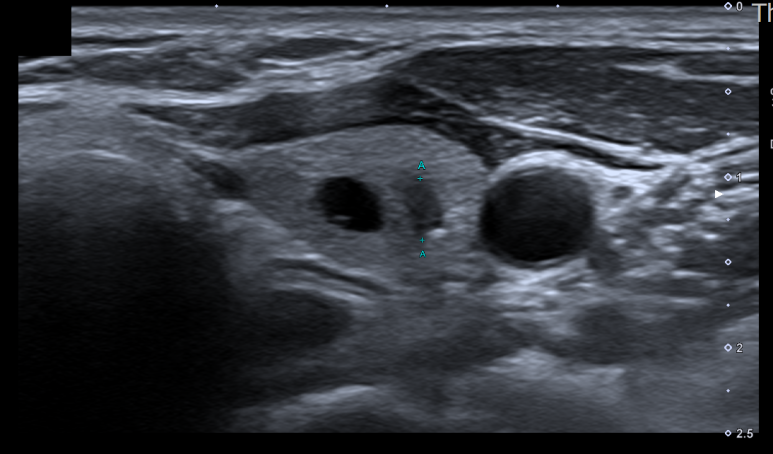

다음 영상은 얼마 전 저희 병원을 방문한 분의 갑상선 초음파 소견입니다. 환자는 1년 전부터 오른쪽 목에 이물감을 호소하고 원인을 확인하기 위해 내원했습니다.

갑상선 초음파

갑상선 초음파

갑상선 초음파 결과 좌갑상선 하부에서 크기가 약 4mm가 되는 아주 작은 결절이 발견되었으며 불규칙한 테두리와 폭보다 높이가 긴 형태(Tallerthanwide), 저 에코성(주변 갑상선 조직보다 어두운 소견)이 확인되어 갑상선암 혐의로 세침흡인검사(조직검사)를 시행하였습니다.세침흡입검사란 초음파를 보면서 주사기(혈액검사를 할 때 사용하는 일반적인 주사기)를 사용하여 결절 세포를 채취하는 것을 말합니다.

안타깝게도 조직검사 결과 갑상선 유두암(Papillary thyroid carcinoma)이 확인되어 치료하고자 본원에서 신속하게 조치를 취하여 대학병원에 진료의뢰하였습니다.